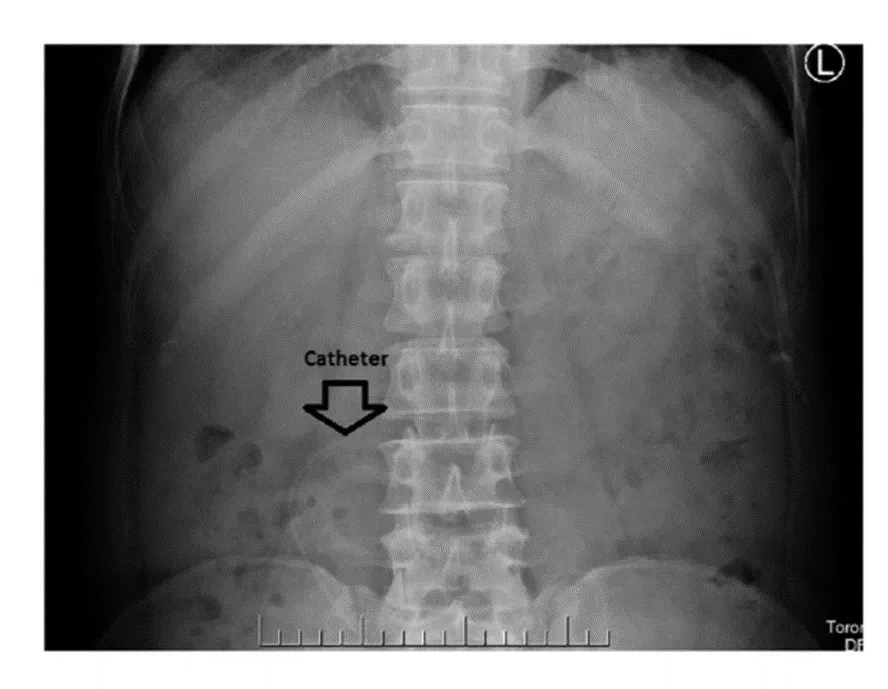

Migração da ponta do cateter.